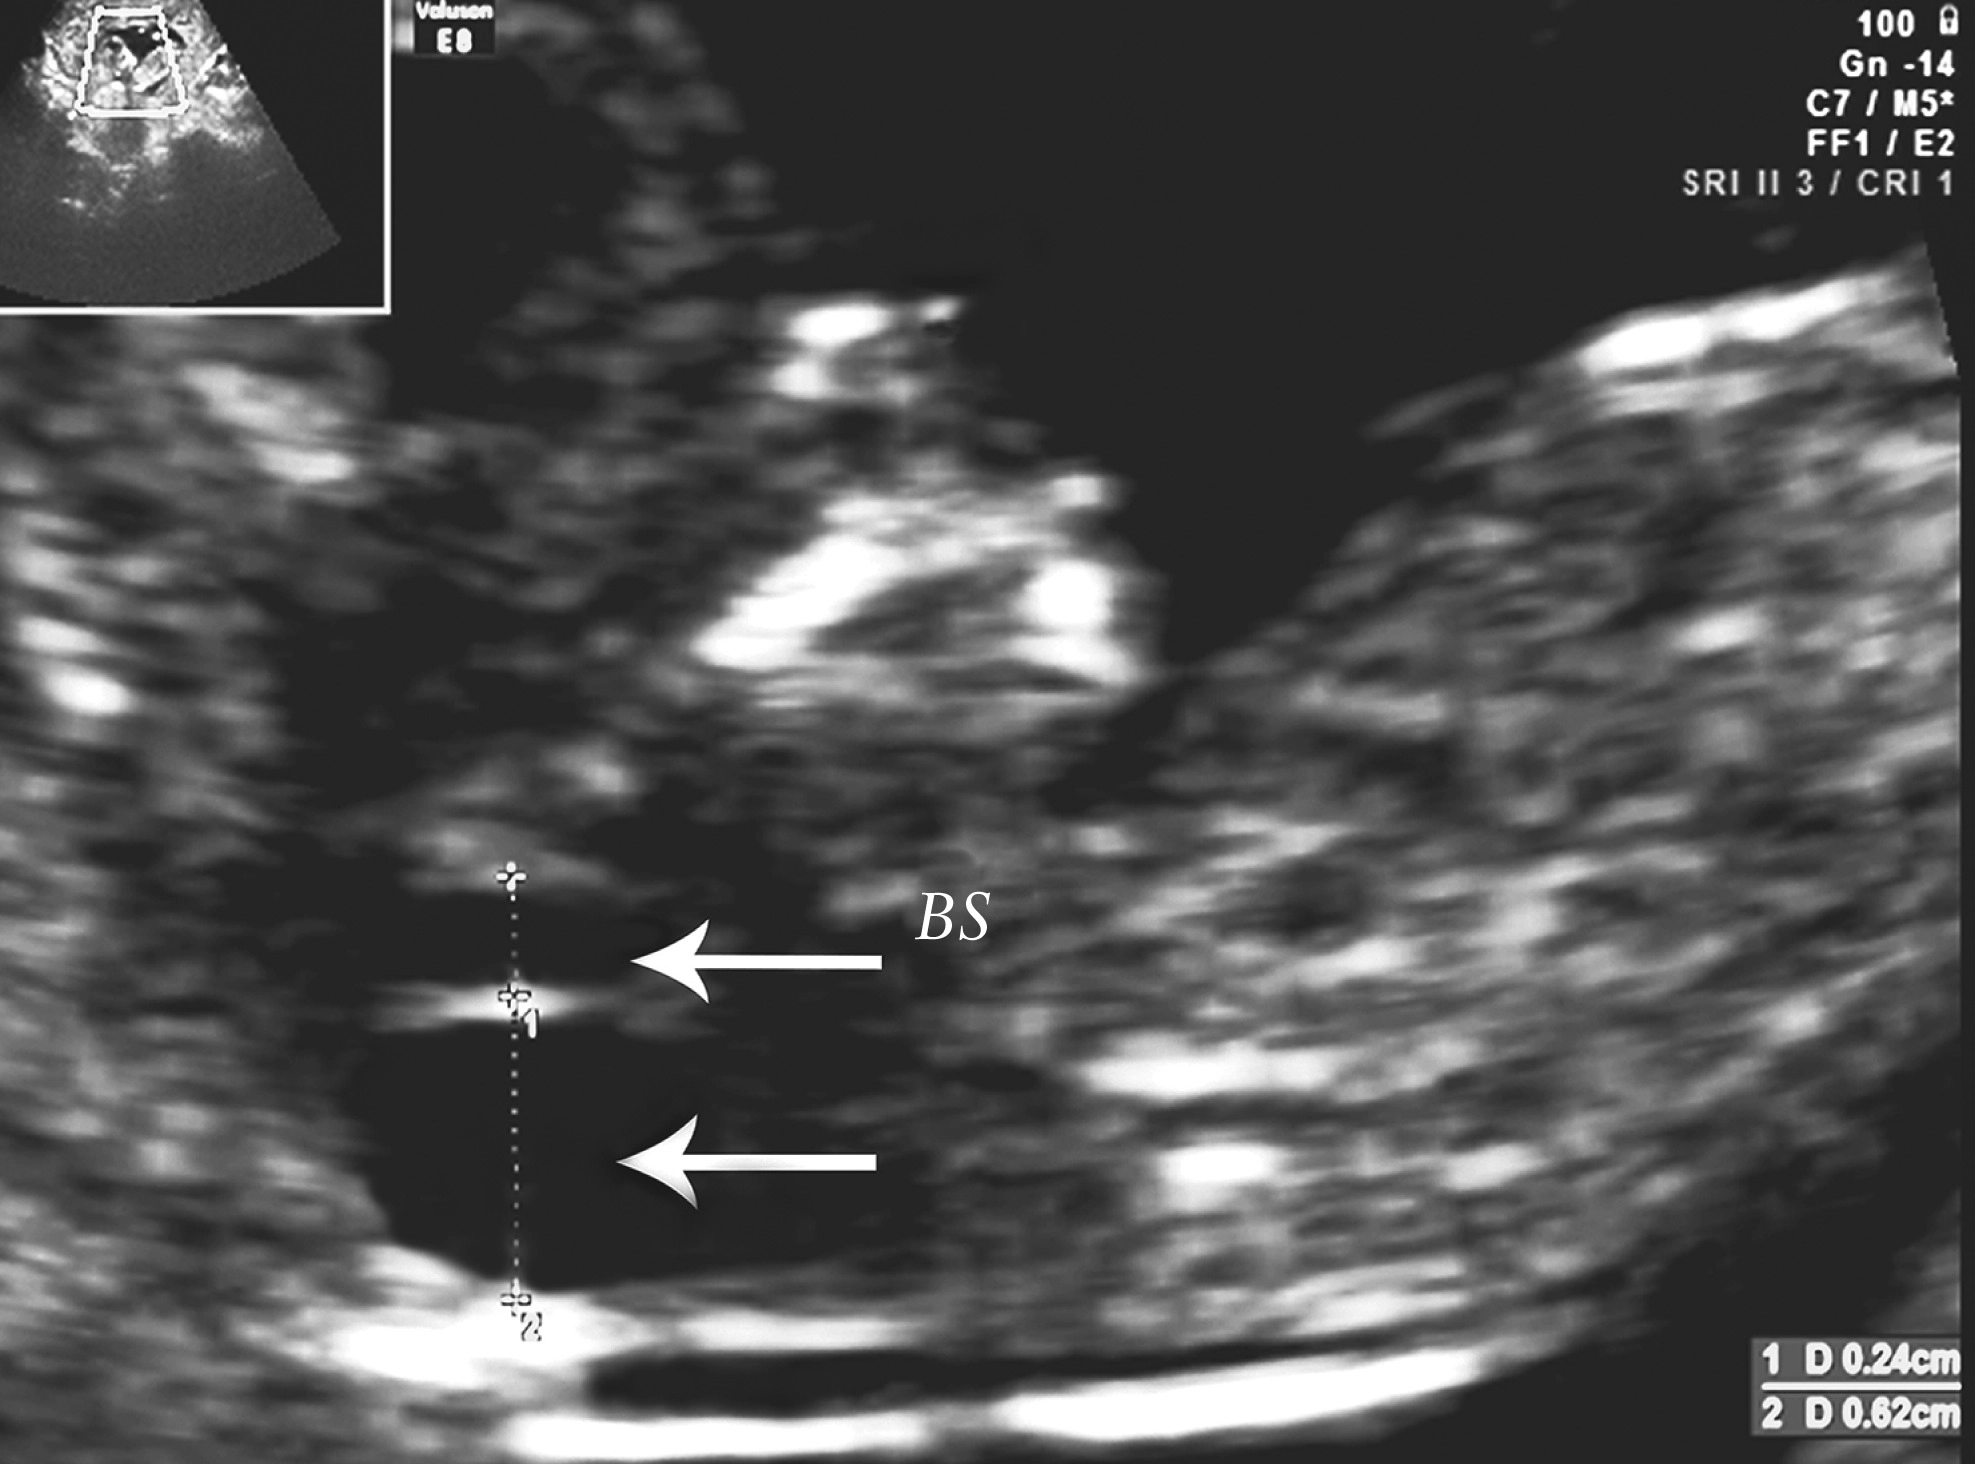

Đo độ mờ da gáy (Nuchal translucency)